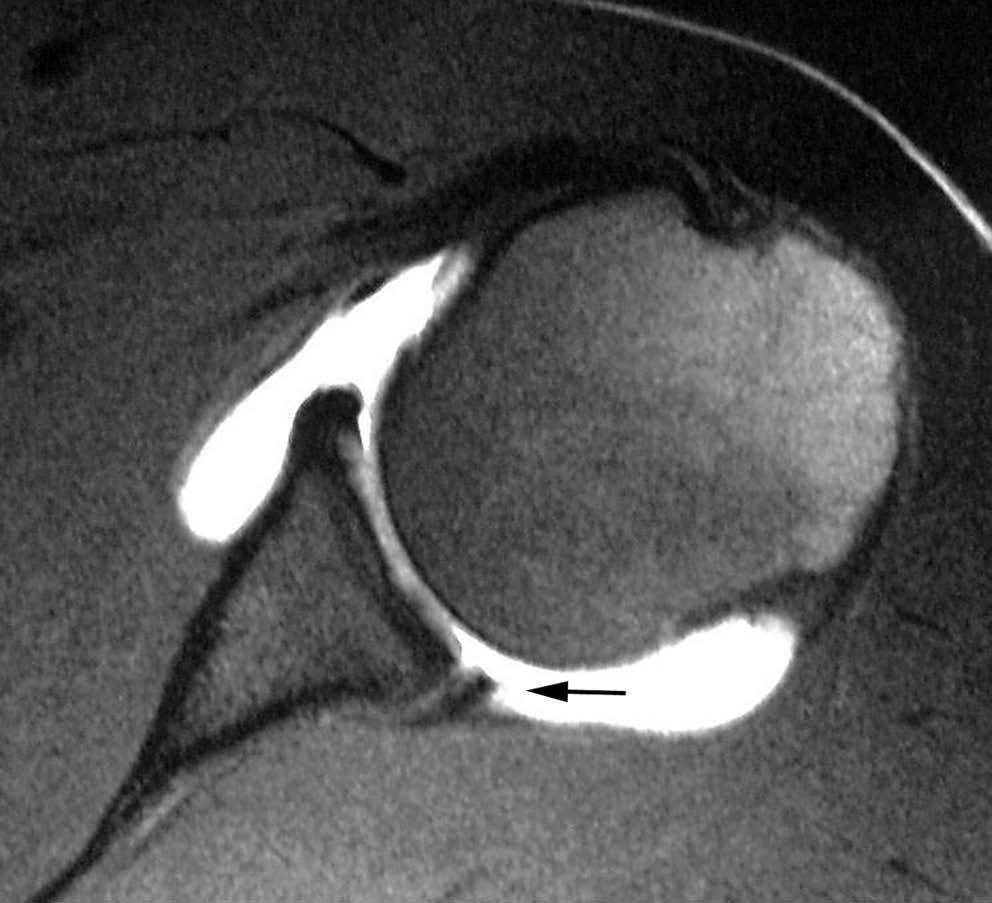

Lesión de Perthes

La lesión de Perthes es similar a la de Bankart, con la excepción de que no existe rotura capsuloperióstica, aunque el periostio puede estar separado del borde anterior del margen glenoideo (fig. 10). Esta lesión puede ser difícil de visualizar, incluso con artrorresonancia, a menos que se obtengan imágenes con la posición de abducción y rotación externa (ABER). En un estudio de 10 casos, verificados quirúrgicamente, Wisher et al17 comprobaron que el 50% de las lesiones de Perthes sólo podían visualizarse en la posición de ABER.

Fig. 10.--Lesión de Perthes. Artrorresonancia T1 con saturación grasa en posición ABER (abducción y rotación externa), donde se observa un arrancamiento parcial del labio glenoideo (flecha) con conservación de la unión capsuloperióstica.